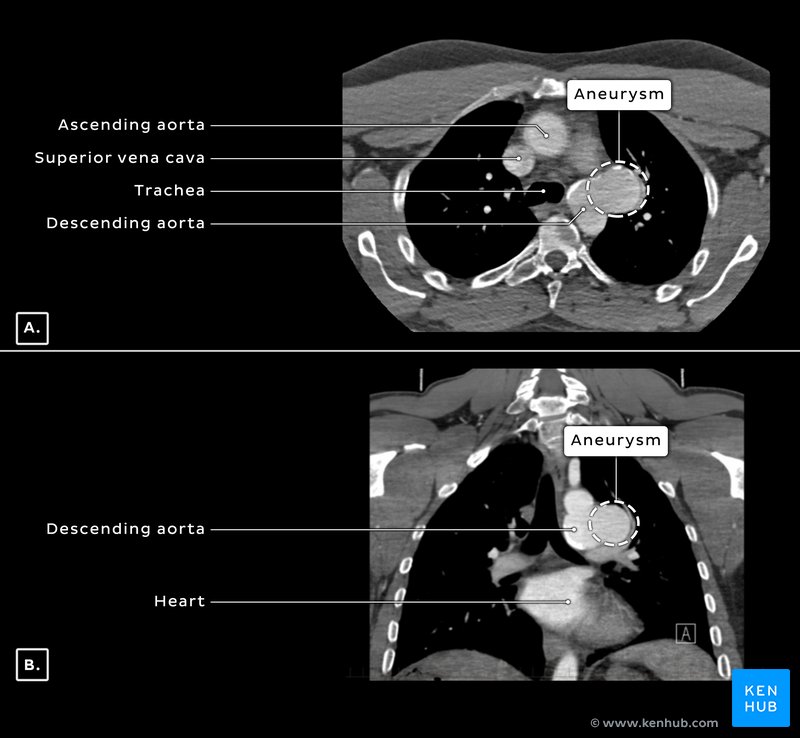

Subsequent computed tomography (CT) imaging of the chest revealed however a 5.4 cm saccular thoracic aneurysm of the aortic arch near to the origin of the left subclavian artery (Figure 3). The presence of peripheral calcifications (Figure 3A, B) in the aneurysm suggested that it was long-standing and therefore an unlikely cause of the patient’s acute symptoms, which remained unknown. There was no indication of perianeurysmal fluid accumulation and no evidence of rupture of the aneurysm.

CT angiogram of the thoracic aorta confirmed the findings and suggested that the proximal margin of the aneurysm lay adjacent to the posterior wall of the left subclavian artery and was 19mm downstream from the posterior wall of the left common carotid artery. The region of the aorta that contained the aorta is known as the isthmus of the aorta.